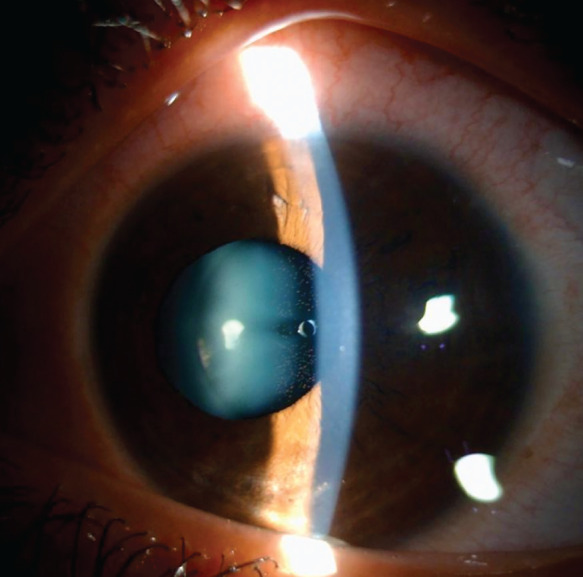

Urrets-Zavalia Syndrome After Posterior Chamber Phakic Intraocular Lens Implantation: An Unusual Complication.